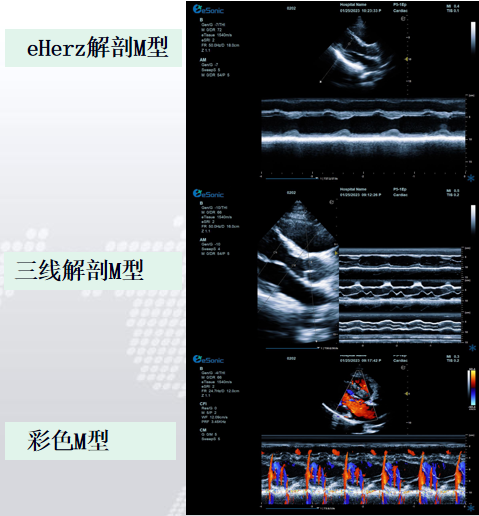

相关心脏应用功能--M型、解剖M型

解剖M型-适用于心尖上翘者、瘦长体形者、室壁瘤形成等...

解剖m型:

不受角度限制,打破技术壁垒不影响M型图谱分辨率。

三线解剖M型:

同一心动周期,多节段评估心功能。

解决节段运动异常和判断同步化运动。

彩色M型:

直观显示室璧运动和血流动力学关系。

更精准判断血流时向,更精准评估心脏功能。